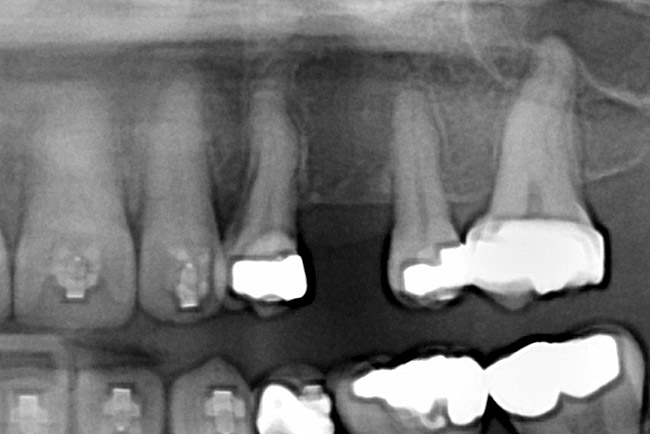

Fig 2 (and Fig 3). Corticotomy SFOT. The patient presented with unesthetic anterior bridgework that was placed at age 14 to compensate for congenitally missing Nos. 7 and 10.

Figure 2

Fig 3 (and Fig 2). Corticotomy SFOT. The patient presented with unesthetic anterior bridgework that was placed at age 14 to compensate for congenitally missing Nos. 7 and 10.

Figure 3